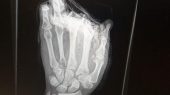

BMXer Kirk Banks from Cambridgeshire was recently involved in a horrific accident whilst performing a heroic act. He dropped me a message via inbox to tell the full story. The unfortunate turn of events happened whilst he was out with friends and noticed his friend’s dog drowning in the lake just off a jetty. Kirk thought quickly and jumped straight in the water to save the dog, but during the whole ordeal, a jetski was passing and didn’t see him which resulted in Kirk losing two of his fingers.

*WARNING* – (GRAPHIC PHOTOS BELOW)